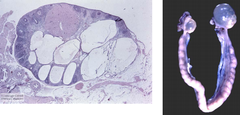

ovotestes

Front

true hermaphrodite

Back